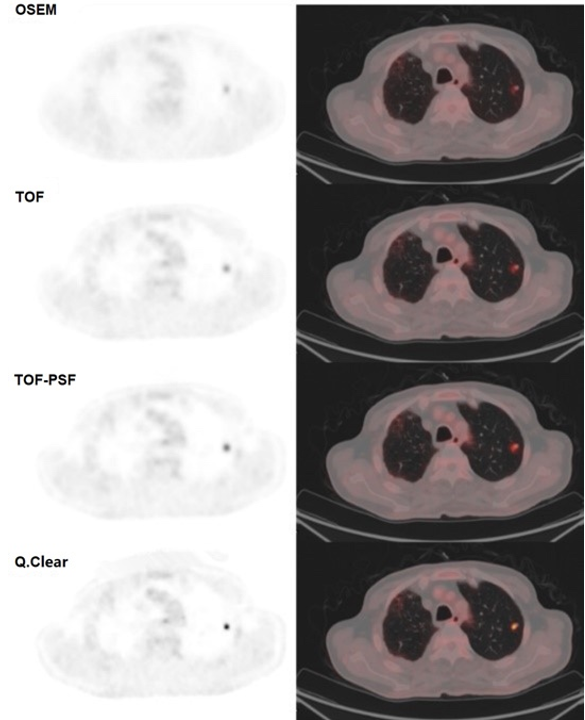

上圖為一個病例使用不同算法重建的肺結(jié)節(jié)(長軸直徑7.2 mm)PET圖像。OSEM,TOF,TOF-PSF,Q.Clear重建圖像的SUVmax分別為1.93、2.62、3.9、7.28,SUVmean分別為0.99、1.42、1.87、3.46。